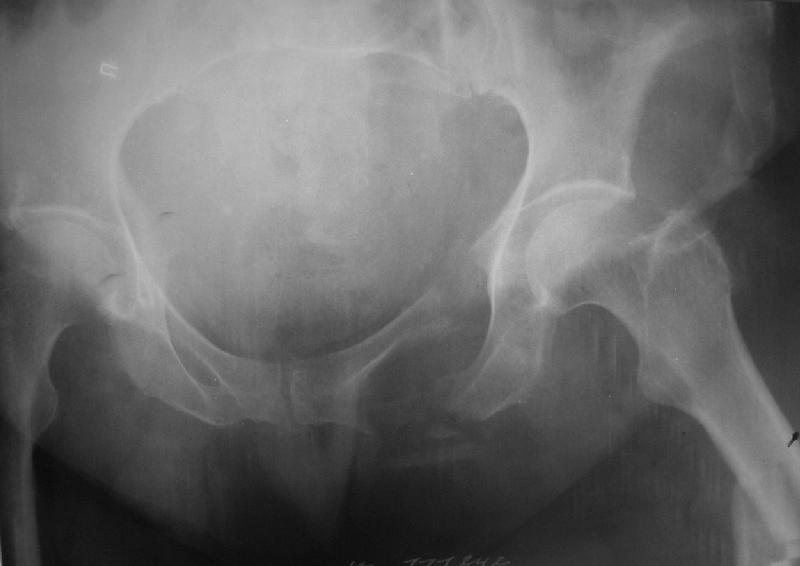

Здравствуйте уважаемые коллеги! Поступила пациентка, 61г, через 1 месяц после травмы, с двусторонним ротационно-нестабильным повреждением тазового кольца: перелом боковых масс крестца с обеих сторон, переломы лонной и седалищной костей слева, отрывные переломы передних остей левой подвздошной кости, сегментарный перелом левой подвздошной кости. Кроме того у пациентки имеется сегментарный перелом левого бедра.

Перелом бедра не вызывает вопросов - планируем блокируемый остеосинтез стержнем, а вот при обсуждении тактики лечения переломов костей таза возник вопрос о необходимости синтеза остей подвздошной кости, учитывая сроки с момента травмы и  наличие остеопороза могут возникнуть технические сложности. Если у кого-нибудь  собственный опыт или ссылки на литературу об отдаленных результатах при не восстановлении сгибательного аппарата бедра?